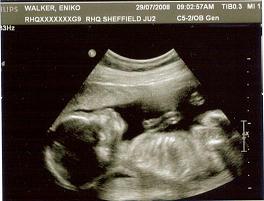

BPD: 45mm

FL: 31mm

HC: 171

Kép a vegtelen koldokzsinor